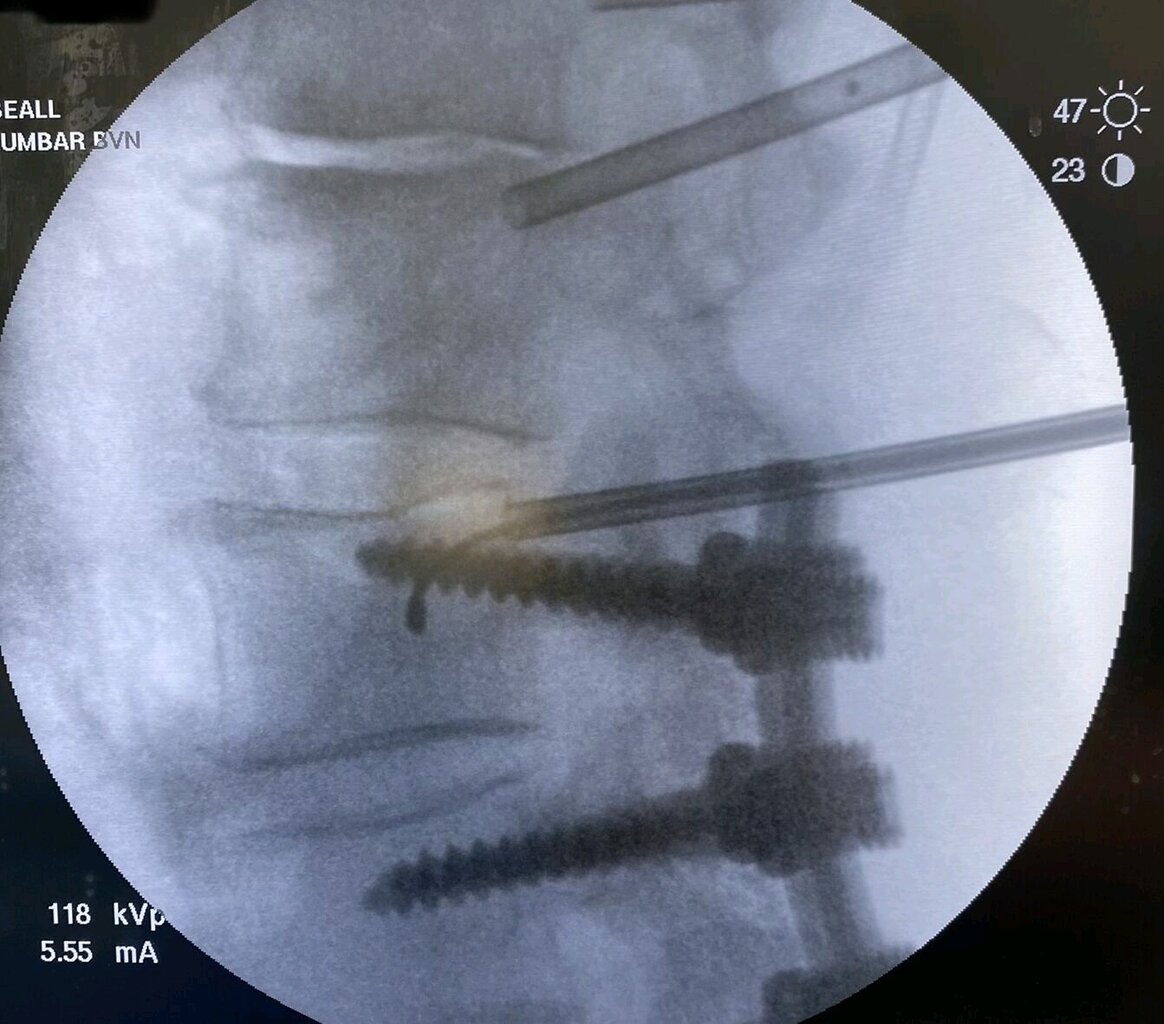

Doug Beall going over the top of screw

image_d763a6f2-305e-4d46-948b-68926a28257620220714_162000.jpg

image_b1888c74-3b51-4a67-af3a-4fc0d9216f5a20220714_161956.jpg

image_5c396b3d-57d1-4a7d-8f47-79217506a40e20220714_161954.jpg

image_c8082d3b-519b-4414-a67e-0560bf23415e20220714_161949.jpg